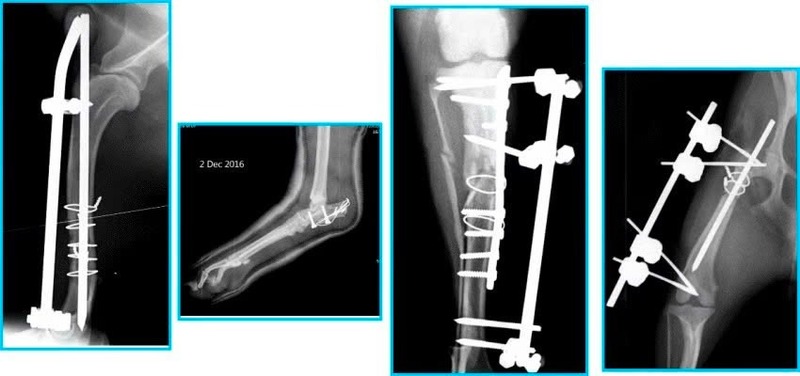

| 2. Khám & chẩn đoán | – Khám lâm sàng: Chân phải sưng, đau, mất khả năng nâng đỡ – Chẩn đoán hình ảnh: X-quang cho thấy gãy sụn khớp chân phải – Kết luận: Cần phẫu thuật cố định khớp |

| 3. Phẫu thuật & hậu phẫu | – Tiếp cận vùng gãy, đóng đinh – buộc chỉ thép để cố định xương – Khâu đóng vết mổ, đặt ống thông tiểu – Theo dõi sinh hiệu, phòng nhiễm trùng – Chăm sóc: vệ sinh vết thương, thay băng, giảm đau, truyền dịch – Hạn chế vận động, bổ sung dinh dưỡng giàu đạm và vitamin B, C |

| 4. Kết quả & phục hồi | – Sau 10 ngày: mèo tỉnh táo, đi lại nhẹ, vết mổ khô – X-quang: Xương liền tốt, không nhiễm trùng – Sau 4–6 tuần: Phục hồi vận động hoàn toàn, khớp ổn định |